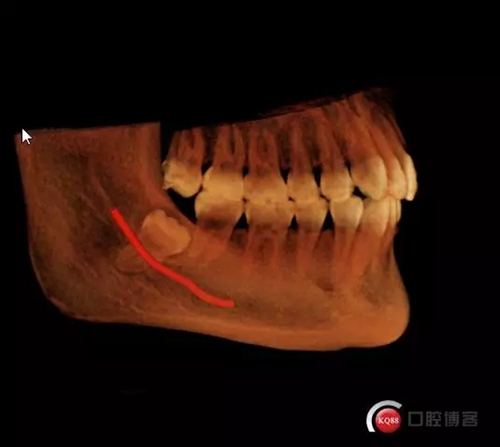

超低位阻生齒緊貼神經(jīng)管伴囊腫

術(shù)前分析:1.冠部骨阻力2.近中阻力

術(shù)后CT,可見神經(jīng)管周皮質(zhì)骨完整,牙槽窩內(nèi)未見神經(jīng)暴露

術(shù)后回訪正常